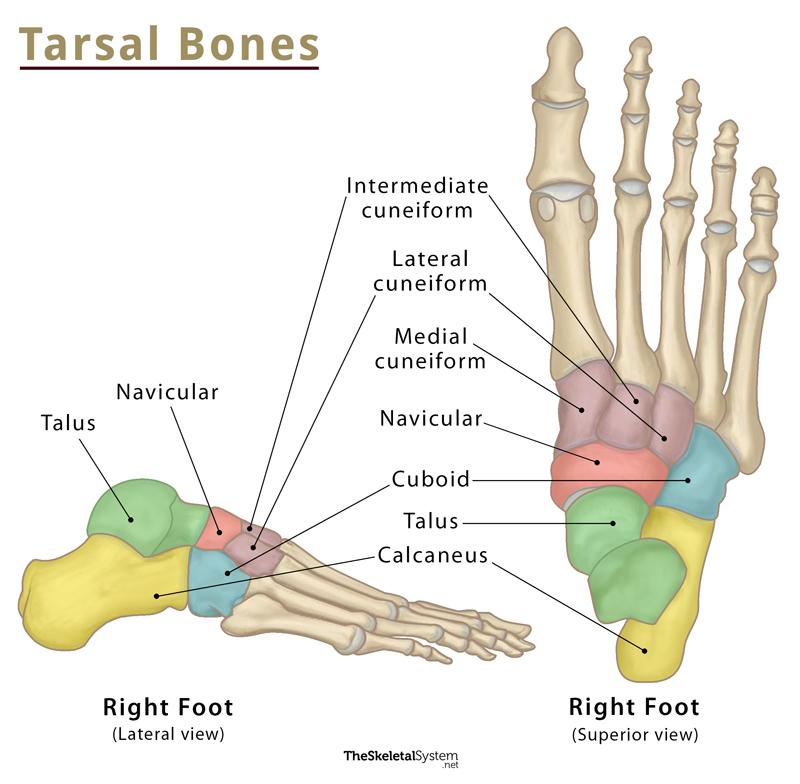

what are the tarsal bones?

cuneiforms

cuboid

navicular

calcaneus

talus

*go in shape of a C and start with C

how many cuneiforms are there?

medial (1st)

intermediate (2nd)

lateral (3rd)

what are the landmarks of the tarsal bones?

talus

calcaneus

navicular tuberosity

does the talus have any muscular attachments?

no muscular attachments, but has ligaments

what is the talus composed of?

head

neck

body

what is the calcaneus?

longest and strongest tarsal bone

what is an important landmark of the calcaneus?

sustentaculum tali

what is the sustentaculum tali?

shelf of calcaneus where tali sits on

what is the navicular tuberosity?

attachment sites for tibialis posterior